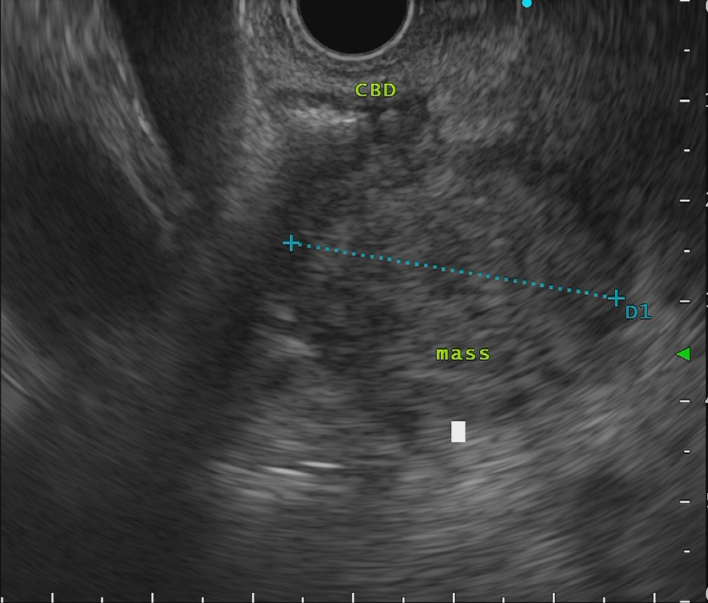

- 超音波内視鏡

術前シミュレーション画像(CT画像)